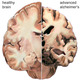

Alzheimer brain

German physician Alois Alzheimer, describes the medical case of Auguste Deter, a patient who had profound memory loss, unfounded suspicions about her family, and other worsening psychological changes. He saw dramatic shrinkage and abnormal depositis in and around her nerve cells in her brain after an autopsy was performed.